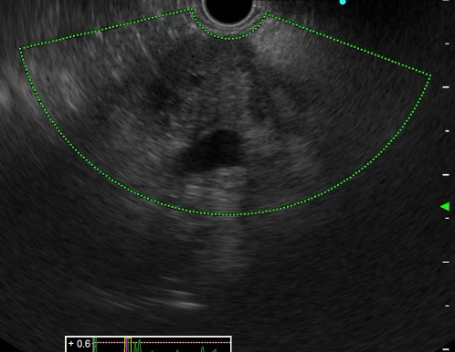

患者,男,58岁,主因“间断进食不畅1月”,就诊于我消化内三科。我院电子胃镜提示:食管下段近贲门处可见巨大隆起性病灶,超声内镜提示:病变起源于固有肌层,最大切面大小约4cmx1.3cm,呈低回声。考虑平滑肌瘤。积极完善相关化验及检查,查无内镜下治疗禁忌症,遂于2023年5月30日行内镜下食管肿物挖出术。